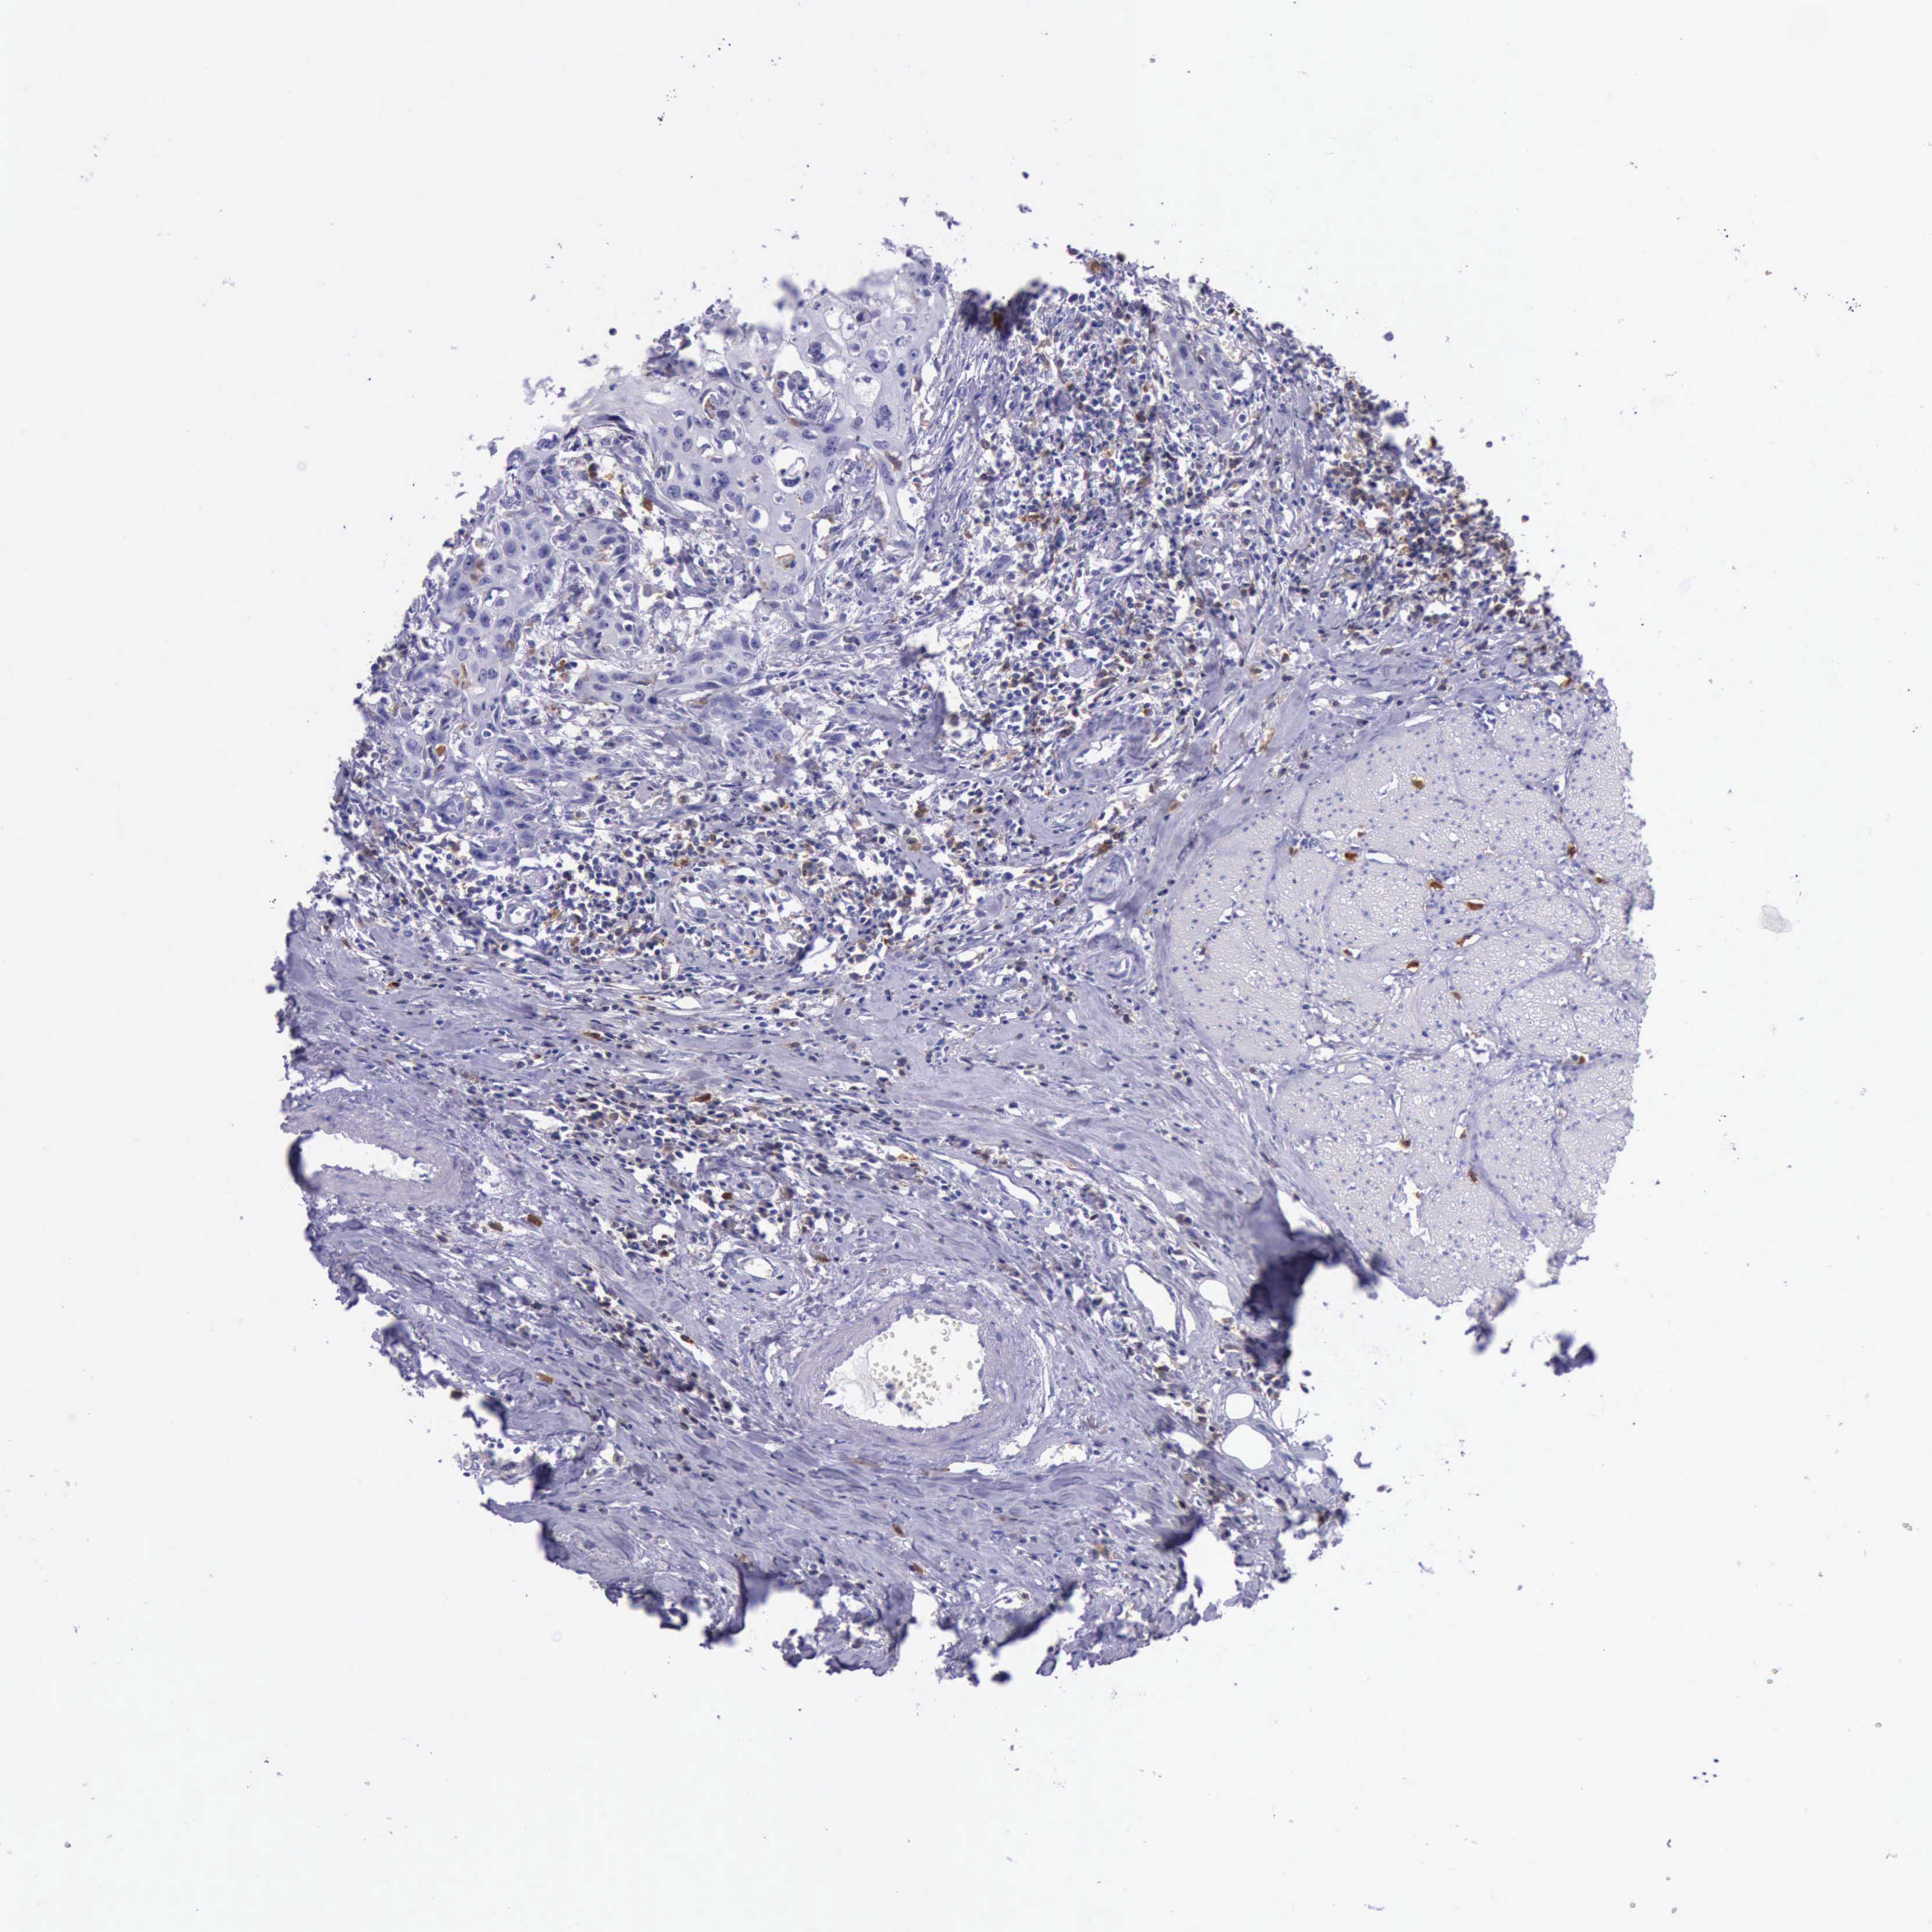

UROTHELIAL CANCER - Protein expressioni

A mouse-over function shows sample information and annotation data. Click on an image to view it in a full screen mode. Samples can be filtered based on level of antibody staining by selecting one or several of the following categories: high, medium, low and not detected. The assay and annotation is described here.

Note that samples used for immunohistochemistry by the Human Protein Atlas do not correspond to samples in the TCGA dataset.

Antibody stainingi

Antibody staining in the annotated cell types in the current human tissue is reported as not detected, low, medium, or high, based on conventional immunohistochemistry profiling in selected tissues. This score is based on the combination of the staining intensity and fraction of stained cells.

Each image is clickable and will lead to virtual microscopy that enables deeper exploration of all samples and also displays staining intensity scores, fraction scores and subcellular localization as well as patient and tissue information for each sample.

Antibody HPA001198

Antibody HPA002028

Antibody CAB016689

Antibody CAB080300

Staining

High

Medium

Low

Not detected

Intensity

Strong

Moderate

Weak

Negative

Quantity

>75%

75%-25%

<25%

None

Location

Nuclear

Cytoplasmic/membranous

Cytoplasmic/membranous,nuclear

Urothelial carcinoma, High grade

Urothelial carcinoma, Low grade

Adenocarcinoma, NOS